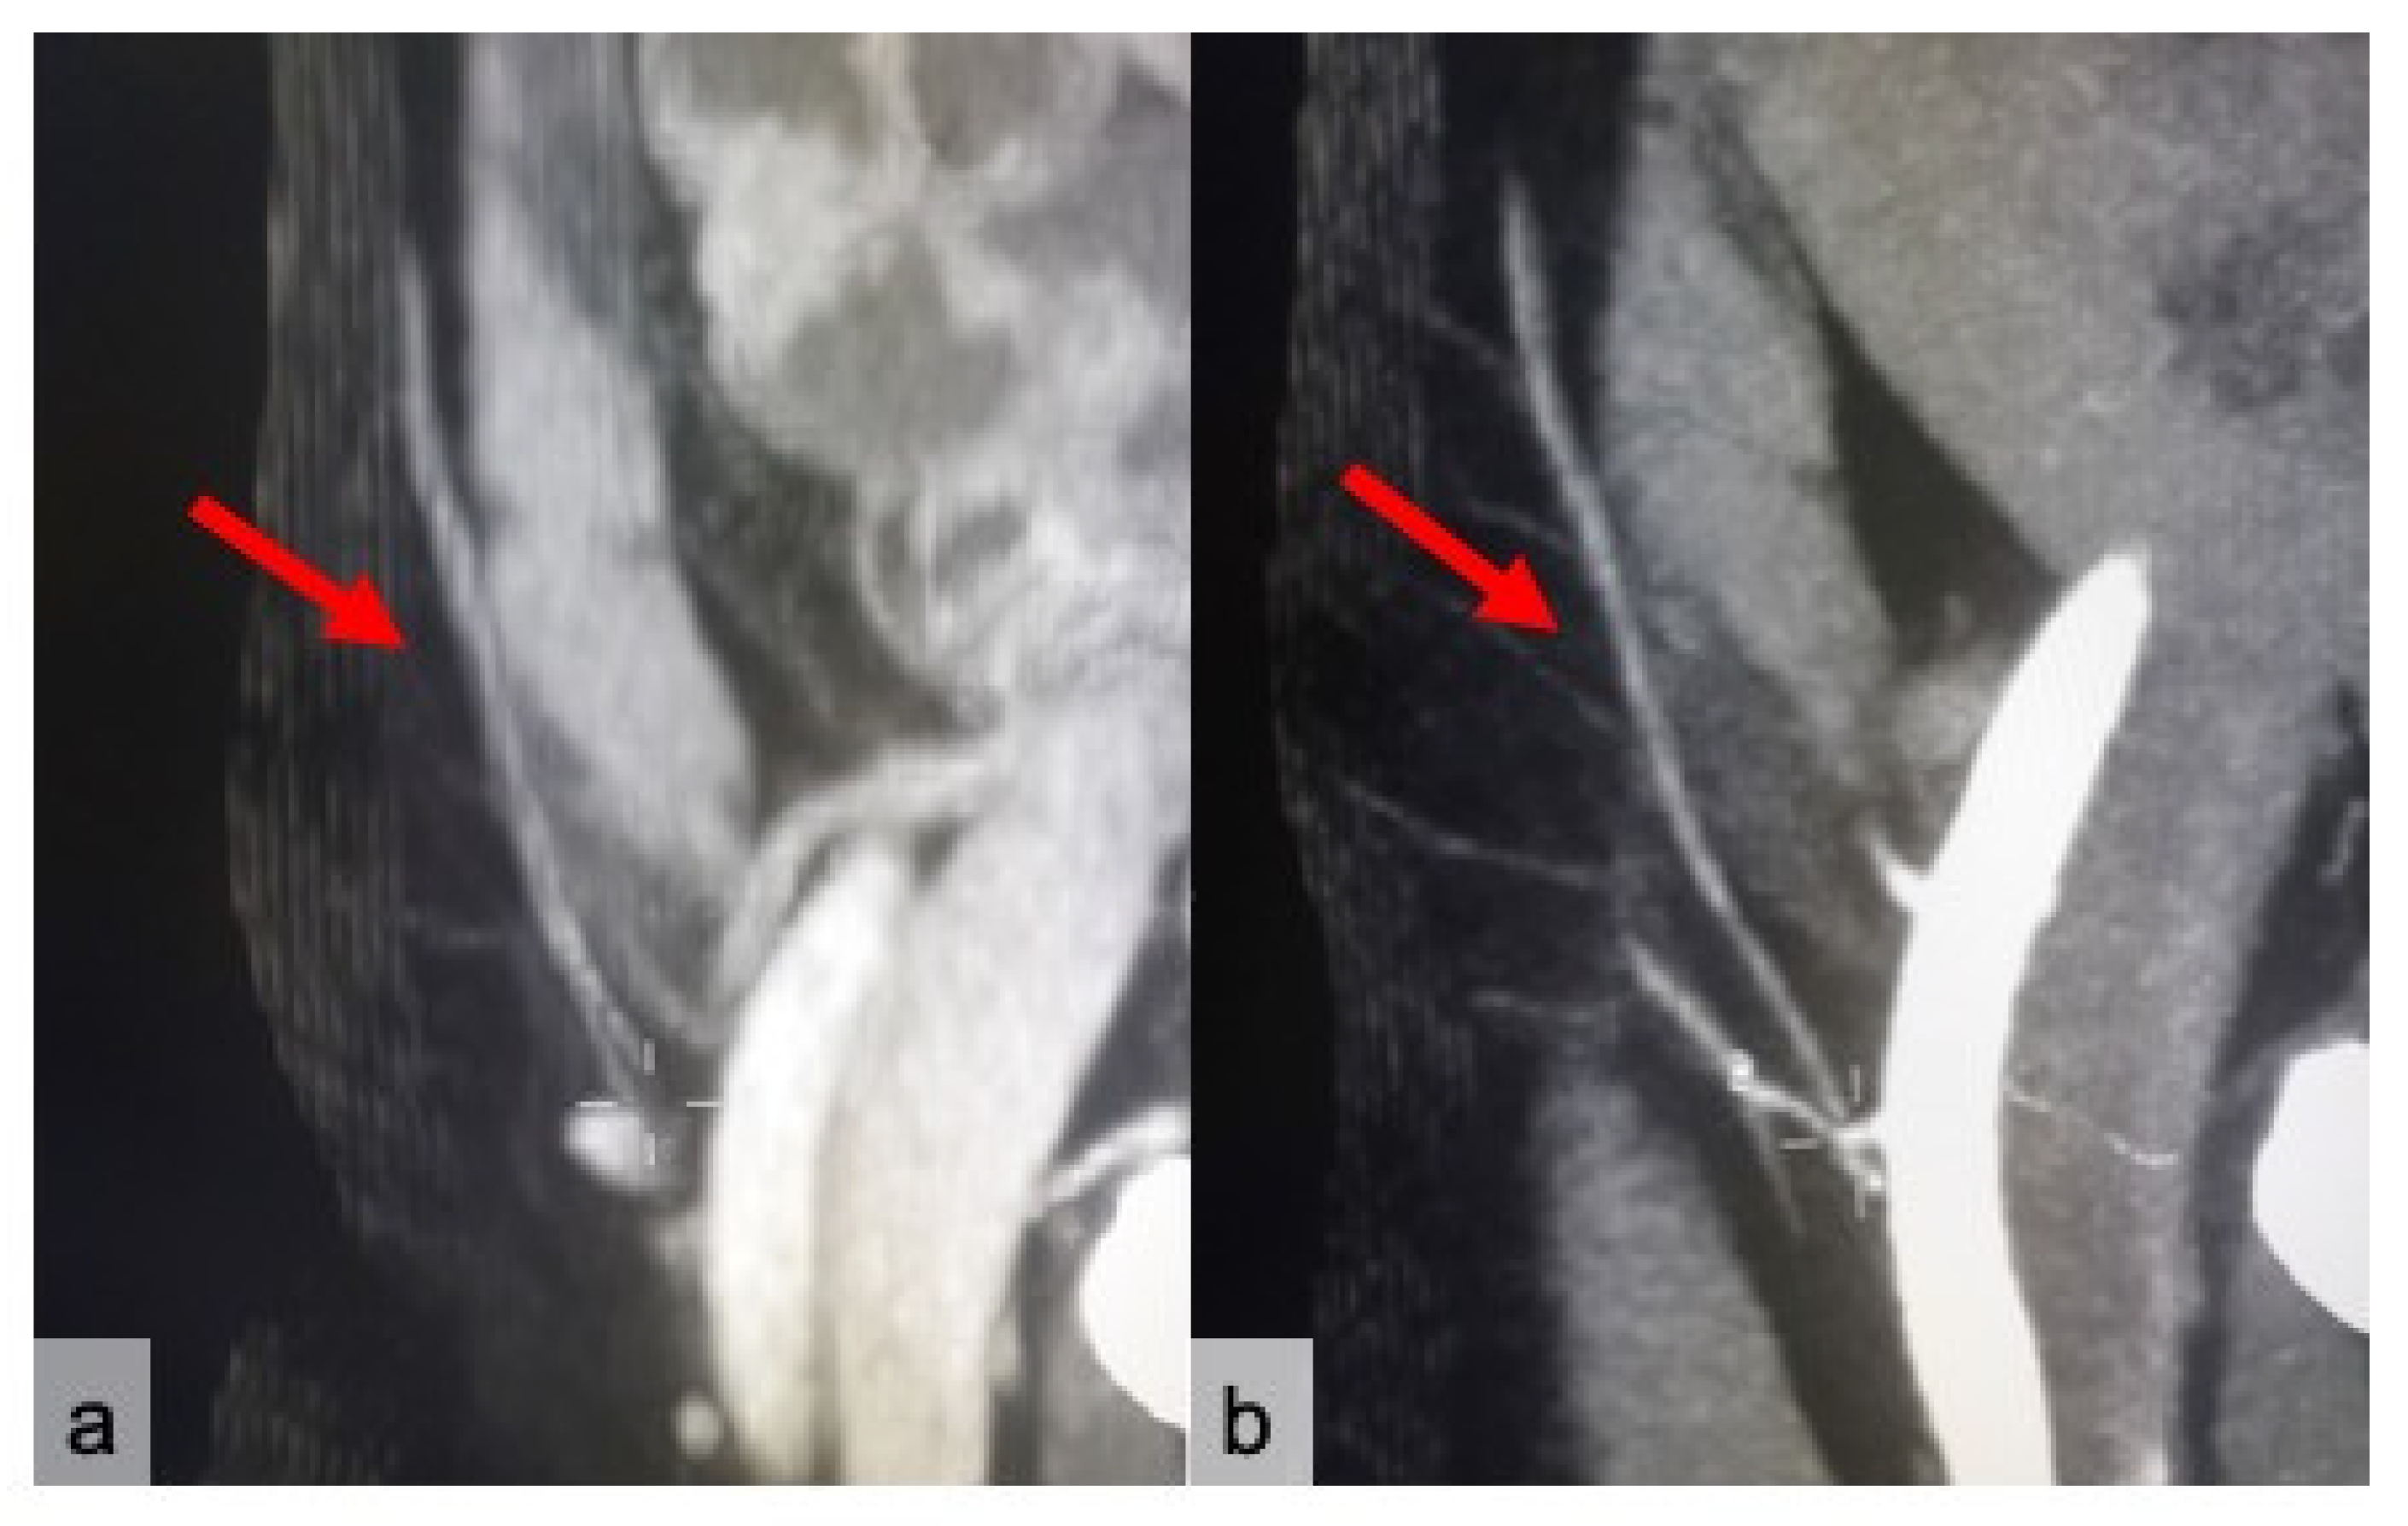

2. Materials and Methods

2.1. CTa and cCT Technique

2.2. Image Analysis

3. Results

4. Discussion